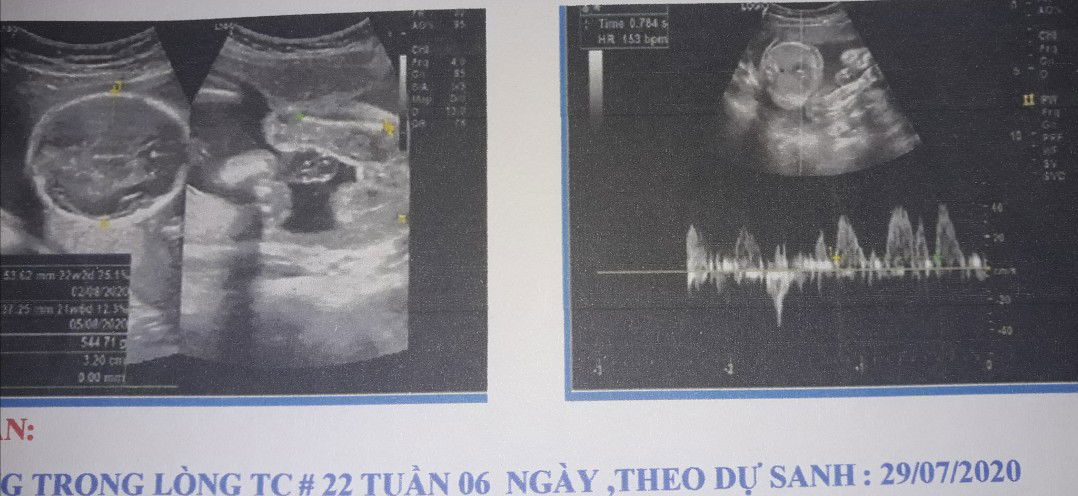

Mom ơi e bé 22 tuần 434gram thì có bé quá ko ạ e đi khám về người nhà bảo là e bé bị nhỏ quá ạ